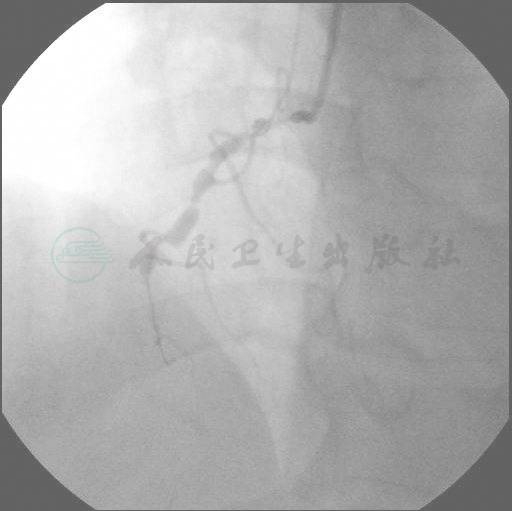

右侧桡动脉途径,6F血管鞘。冠状动脉造影提示:患者存在颈部大血管变异,为食管后无名动脉(图1、图2)。RCA(选择AR1)存在右冠脉弥漫病变,缘支发出后完全闭塞,LM和LAD基本正常,LCX弥漫性病变,远端95%狭窄,LM经间隔支对RCA提供侧支循环(图3、图4)。